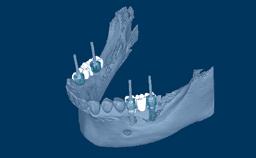

Com a introdução de scanners intraorais e a ampla utilização de próteses implantossuportadas produzidas usando CAD/CAM - ou Fabricação Auxiliada por Computador/Fabricação Assistida por Computador - é possível digitalizar as posições dos implantes diretamente na boca do paciente. Fazer varreduras intraorais de implantes, em vez de digitalizar modelos de gesso com base em moldagens convencionais, economiza várias etapas no processo restaurador. Com menos etapas, há também menos risco de erros e discrepâncias. Este módulo focará sobre as aplicações de escaneamento intraoral dos implantes dentários.